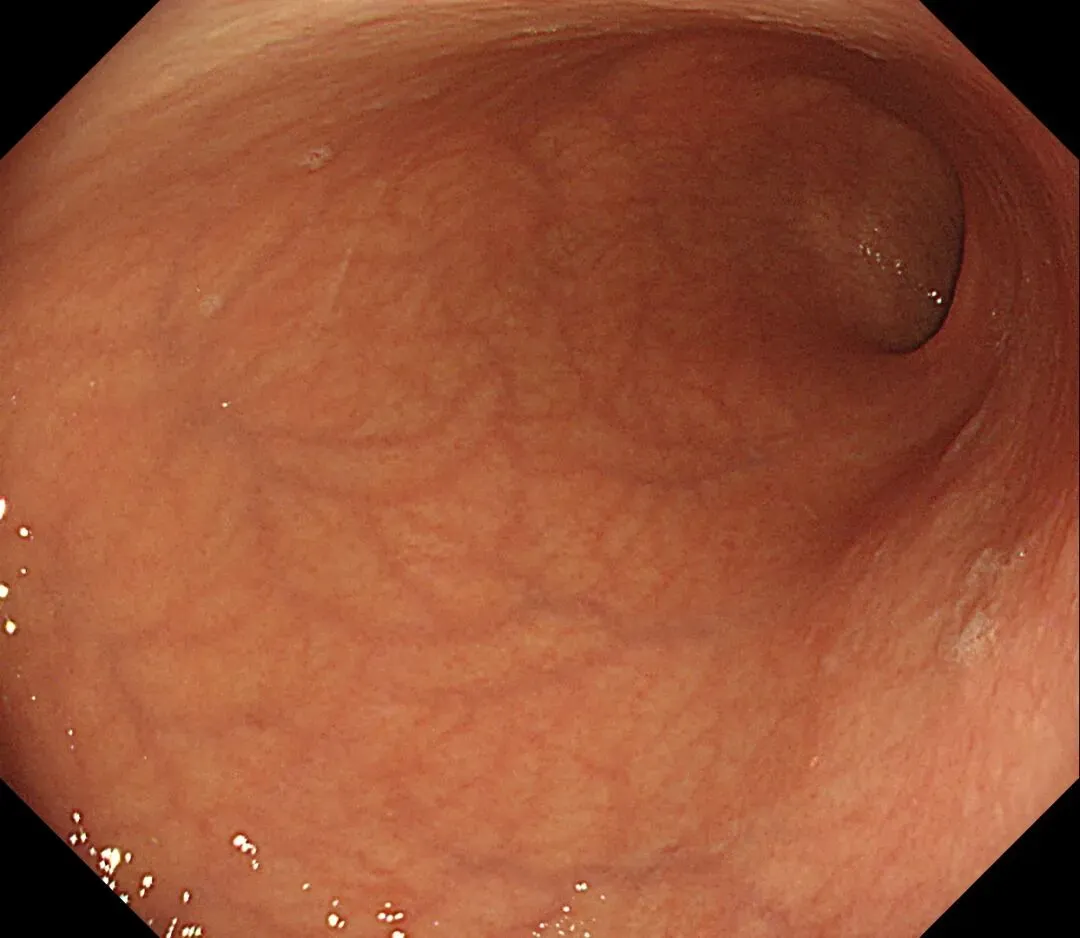

进镜至贲门观察到“花环征”,提示存在AIG的可能,带学生的内镜老师这个moment可以装一把,不过。。。偶尔也有翻车的时候,以下这例是在“Hp现症感染C3萎缩”患者的花环

有待进一步研究。。。